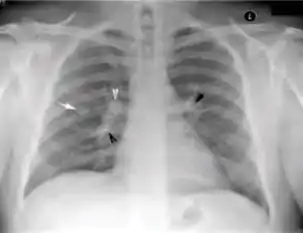

Chest X-ray of a person with advanced tuberculosis: Infection in both lungs is marked by white arrow-heads, and the formation of a cavity is marked by black arrows.

2. Any cavitary lesion - Lucency (darkened area) within the lung parenchyma, with or without irregular margins that might be surrounded by an area of airspace consolidation or infiltrates, or by nodular or fibrotic (reticular) densities, or both. The walls surrounding the lucent area can be thick or thin. Calcification can exist around a cavity.